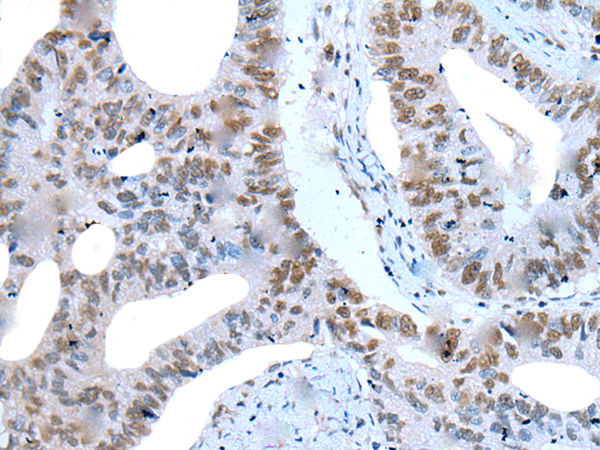

IHC positive control:

IHC Recommend dilution:

20-100